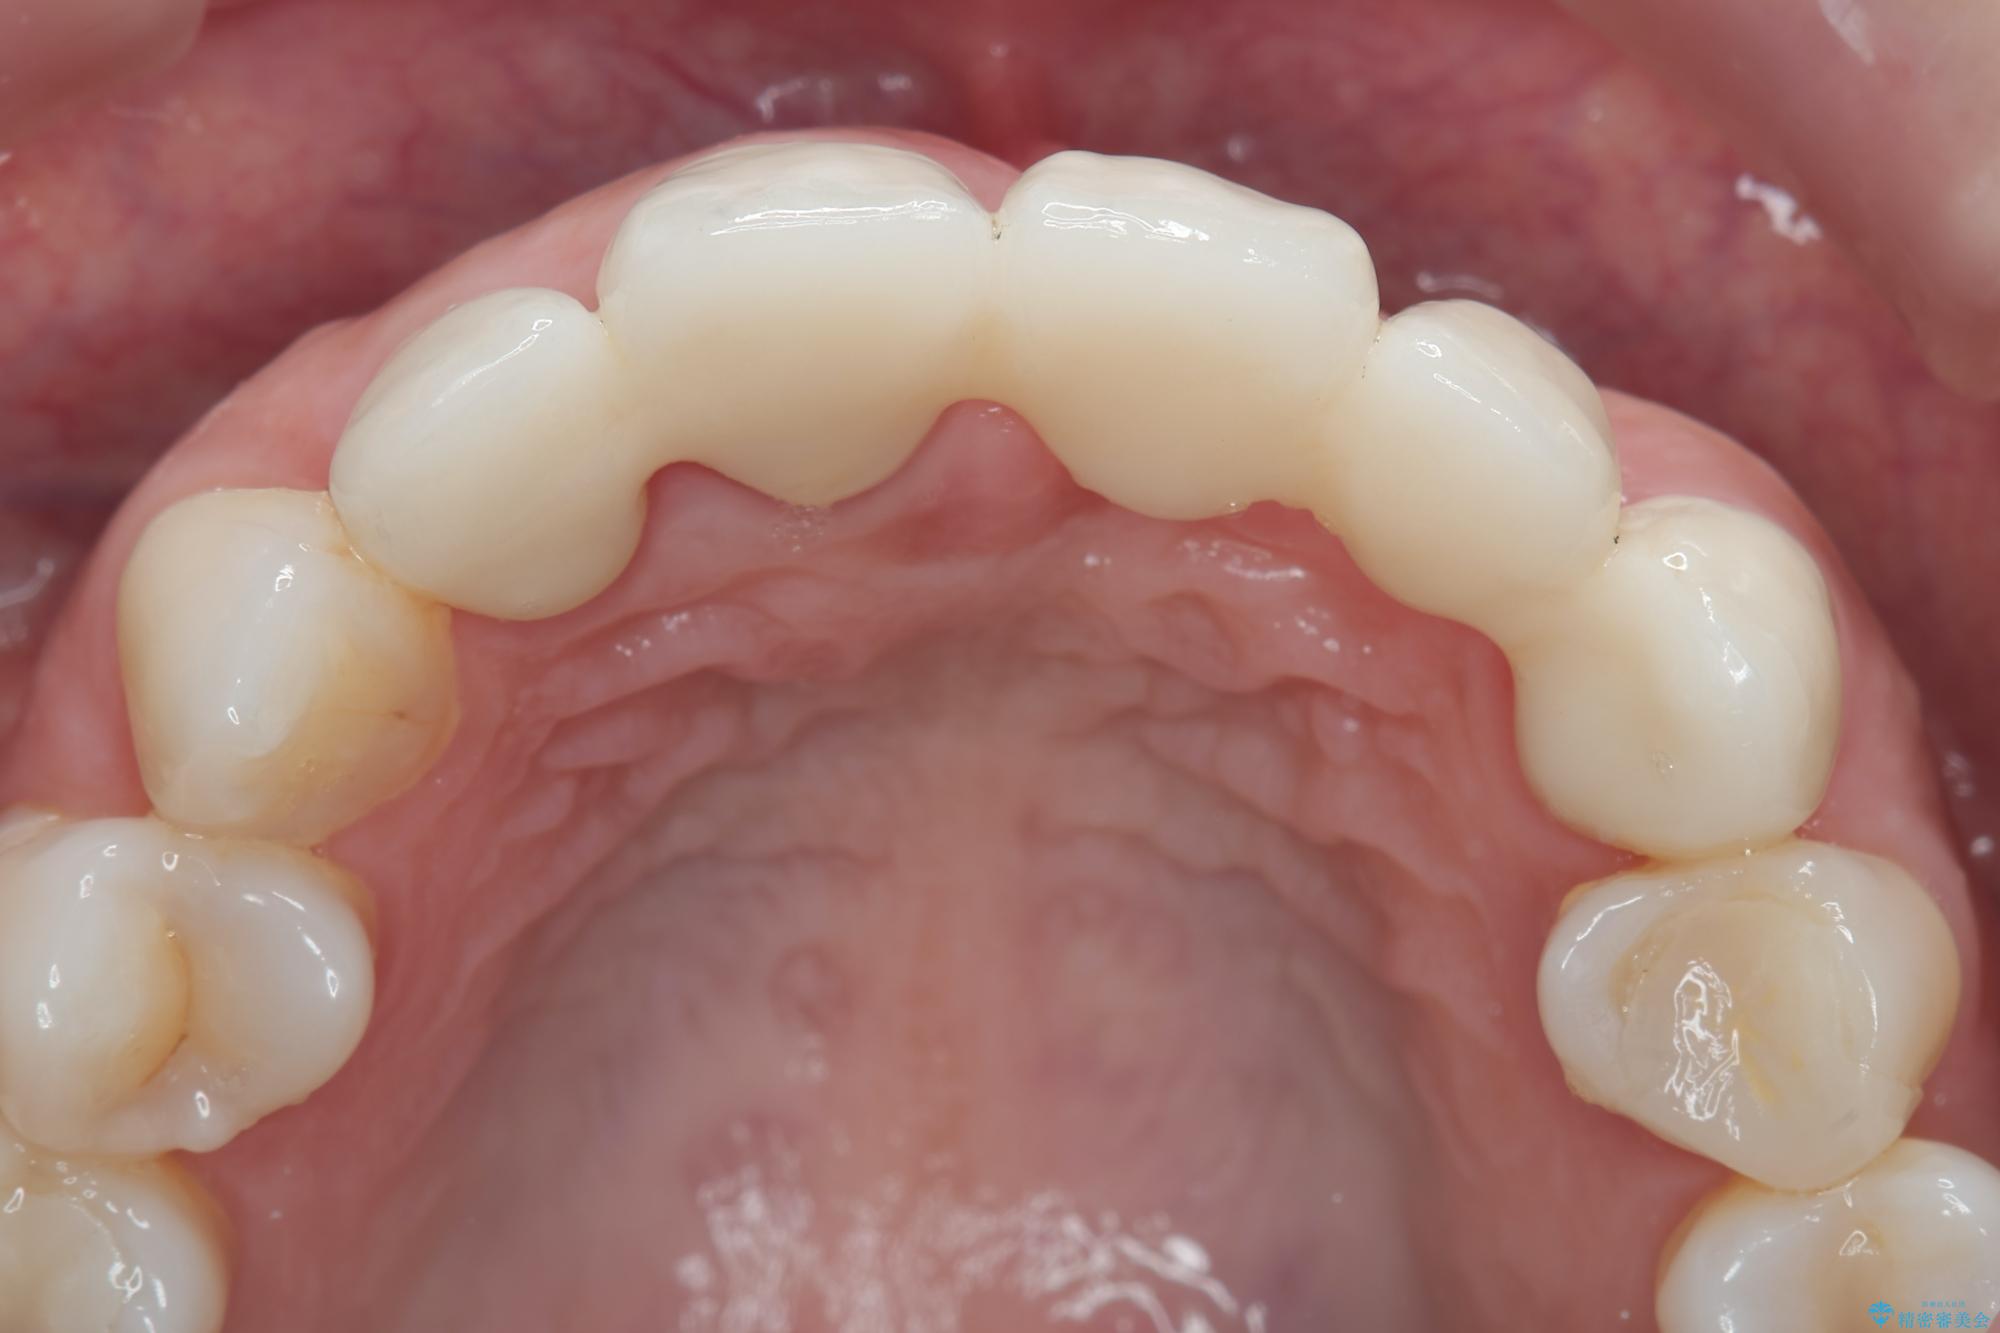

治療中

歯槽堤保存術を併用したブリッジ治療 治療中画像 歯槽堤保存術を併用したブリッジ治療 治療中画像 歯槽堤保存術を併用したブリッジ治療 治療中画像 歯槽堤保存術を併用したブリッジ治療 治療中画像 歯槽堤保存術を併用したブリッジ治療 治療中画像 歯槽堤保存術を併用したブリッジ治療 治療中画像 歯槽堤保存術を併用したブリッジ治療 治療中画像